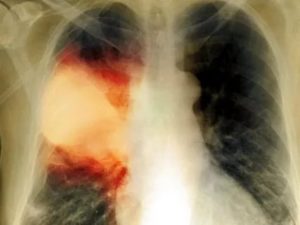

Как выглядит пневмония на снимке (рентгеновском), если она крупозного вида:

- субтотальные, тотальные затемнения с одного или же двух краев;

- смещение средостения в сторону предельного поражения;

- изменение физического поражения куполов диафрагмы;

- закупорка реберно-диафрагмальных синусов жидкостью;

- полное деформирование легочного рисунка;

- тяжистость корней легких.

Выявить особенности крупозного воспаления возможно на рентгенограмме. Однако при патологии медицинским стандартом диагностики считается рентгенография в двух проекциях (прямая и боковая). Такого рода список процедур совершают для оценки численности пораженных частей легких и исследования состояния средостения.

- Тотальные. Патологический процесс охватывает всю область лёгочной ткани. Сильная пневмония слева

Данной форме характерно формирование больших участков поражения легочной ткани. Патологический процесс может охватывать как одно, так и оба легких. На иллюстрации ниже показана тяжелая форма крупозной пневмонии.

При слиянии отдельных очагов воспаления легочной ткани возникает крупозная пневмония. Фото рентгеновского снимка, сделанного при этой форме заболевания, наглядно показывает отличия.

Как правило, при крупозной форме воспаления легких поражается одна или несколько долей легких сразу. Это создает серьезную угрозу жизни пациента.

На рентгене крупозная форма болезни проявляется следующими признаками:

- Ярко выраженные крупные тени, затрагивающие доли легкого целиком. Могут быть поражены оба легкого.

- Средостение смещается в сторону наиболее воспаленного легкого.

- На куполах диафрагмы отчетливо видны признаки деформации.

- Рисунок легочной ткани может не просматриваться.

Крупозная пневмония легче всего выявляется при рентгенологическом исследовании. Тем не менее для постановки точного диагноза врачи предпочитают делать рентгеновские снимки в двух проекциях. Это дает им возможность определить число пораженных воспалением сегментов органа и определить состояние средостения.

- Крупозная пневмония. Наблюдаются изменения нормального легочного рисунка, жидкость в полости плевры, признаки инфильтрации одной из долей легкого, расширение корней. По мере развития воспалительного процесса выраженность изменений и интенсивность окраски затемнений усиливается.